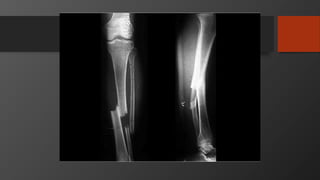

Tibia Shaft Fractures

• Mechanism

• Low energy usually torsional injury

• High energy, e.g. road-traffic accident

Tibial Plateau Fracture

• Imaging:

• X-Ray: AP, Lateral

• Full length

• Knee and ankle also

• Operative

• Displaced or open

• If displaced and closed

• Standard treatment is reamed IM nail

• If open frx – treat as per open fracture guidelines